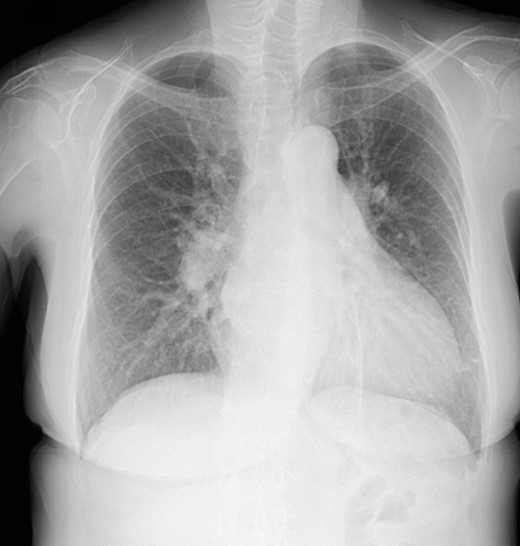

The patient was followed up as an outpatient since 2010 for incomplete AVSD and congestive heart failure by the Cardiovascular Surgery Department at our hospital. She did not wish to undergo surgery; therefore, we continued to follow her as an outpatient. Mitral regurgitation (MR) III-IV and mitral valve deviation was detected by echocardiography at approximately 2022, with worsening heart failure symptoms (New York Heart Association (NYHA) class III status). Echocardiography revealed an ejection fraction (EF) of 65%; severe MR; mean pulmonary artery pressure (PAP) of 32 mmHg; left-to-right shunt flow; left ventricular dysfunction (LVDd) of 48 mm; LVDs, 32 mm; and cleft mitral valve (Fig. 1). Chest radiography revealed a cardiothoracic ratio (CTR) of 58% and a costophrenic angle (CPA) sharp (Fig. 2). Cardiac catheterization revealed a Qp/Qs ratio of 2.6. Therefore, we performed a mitral valve repair and patch closure of the primum ostium defect.